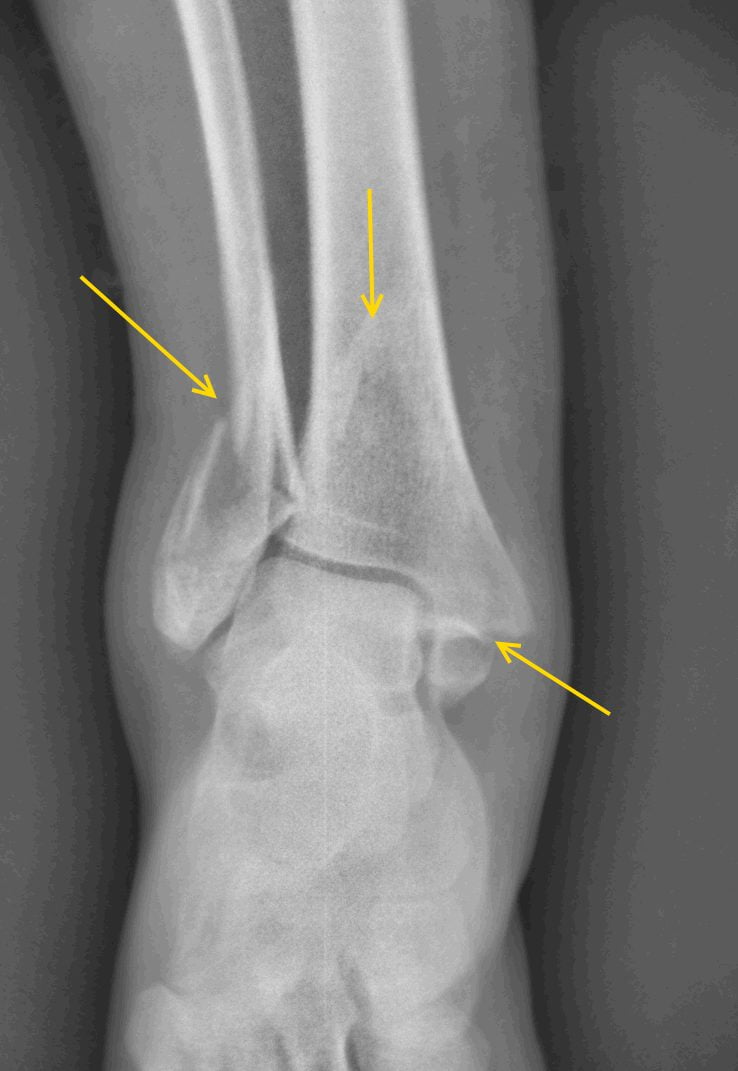

Перелом – это достаточно распространенный вид травмы голеностопного сустава, на долю которого приходится около 15% от общего числа механических повреждений костно-суставных сегментов опорно-двигательного аппарата. Происходит опосредованное воздействие травмирующей силы, то есть при жестком фиксировании задней части стопы ее передний отдел продолжает движение. Травма (перелом) голеностопа возможна при падении с высоты, в результате неудачного приземления при выполнении физических упражнений, катании на лыжах, коньках. При получении травмы дальнейшее перемещение или движение человека становится весьма ограничено, так как голеностопный сустав болит. Что делать?

Не следует производить пораженной нижней конечностью какие-либо физические действия. Человеку нужна помощь медицинского работника и абсолютный покой, так как характер повреждения можно определить лишь при рентгенологическом исследовании. Нужно немедленно доставить пациента в ближайшее медицинское учреждение или вызвать Скорую помощь.